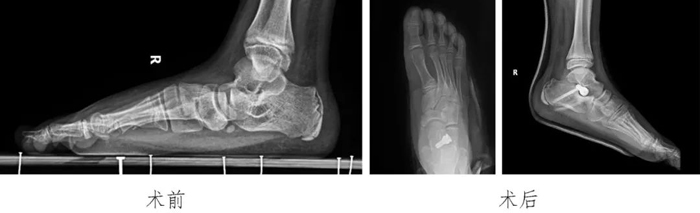

4?青少年扁平足:

通過跗骨竇區(qū)微創(chuàng)小切口放置距下關(guān)節(jié)制動(dòng)器治療青少年的扁平足,患兒術(shù)后足弓恢復(fù),得到患兒家長的認(rèn)可。